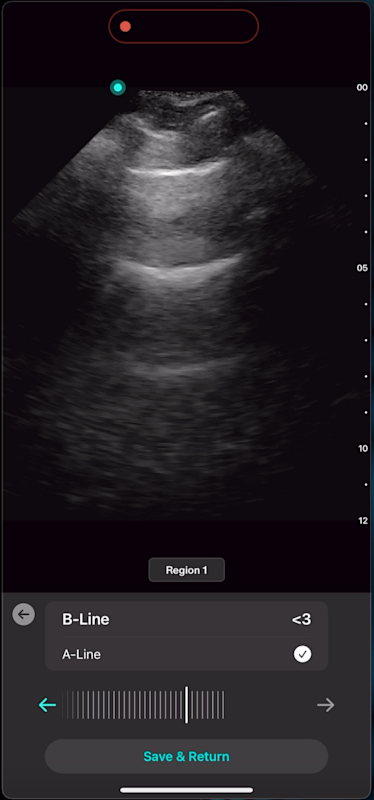

With Lung AI, you can determine the presence or absence of A-lines, B-lines, pleural effusion, and consolidation/atelectasis reliably in seconds.

Lung ultrasound demonstrates high diagnostic accuracy, with a sensitivity of 94% and specificity of 92% for detecting acute cardiogenic pulmonary edema (ACPE) through B-line quantification. [9] AI performs similarly, achieving sensitivity/specificity of 91%/81% for A-lines, 94%/77% for detecting 3+ B-lines, and 84%/86% for 5+ B-lines. Diagnostic performance is also high for other findings, including pleural effusion (97%/91%) and consolidation/atelectasis (97%/94%)